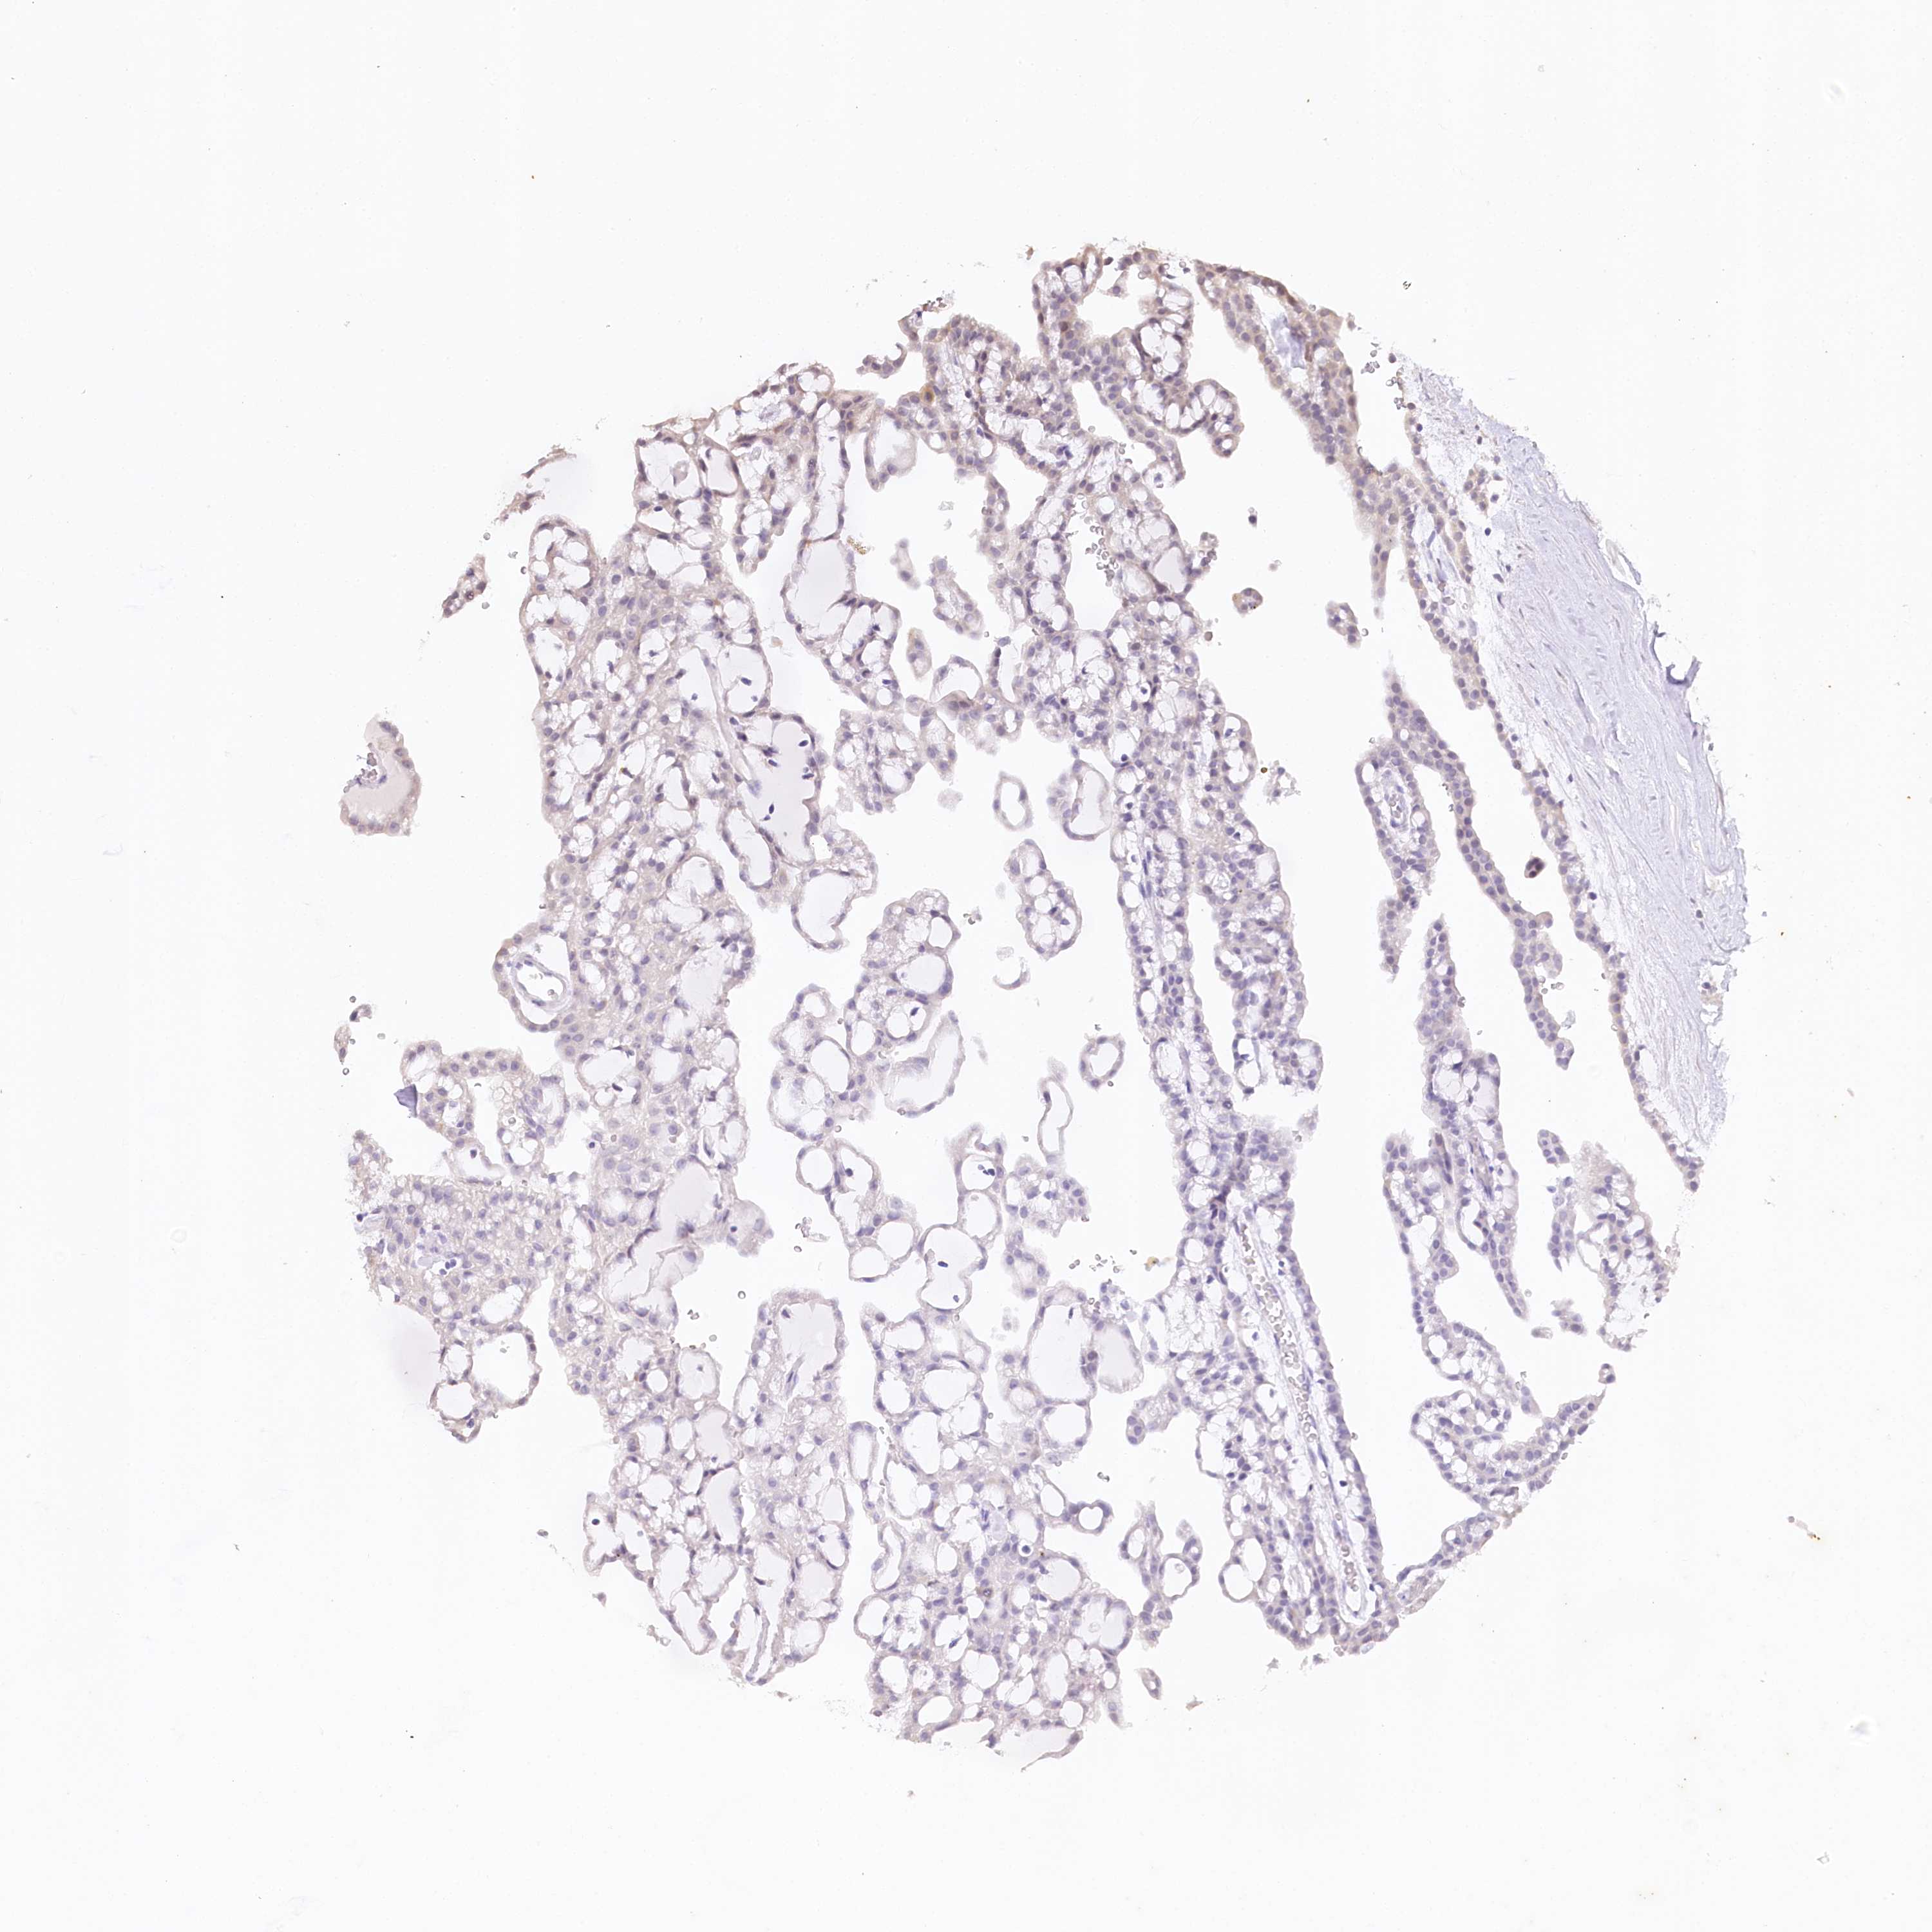

KIDNEY RENAL PAPILLARY CELL CARCINOMA (TCGA) - Interactive survival scatter ploti

The Survival Scatter plot shows the clinical status (i.e. dead or alive) for all individuals in the patient cohort, based on the same data that underlies the corresponding Kaplan-Meier plots. Patients that are alive at last time for follow-up are shown in blue and patients who have died during the study are shown in red.

The x-axis shows the expression levels (FPKM) of the investigated gene in the tumor tissue at the time of diagnosis. The y-axis shows the follow-up time after diagnosis (years). Both axes are complimented with kernel density curves demonstrating the data density over the axes. The top density plot shows the expression levels (FPKM) distribution among dead (red) and alive patients (blue). The right density plot shows the data density of the survived years of dead patients with high and low expression levels respectively, stratified using the cutoff indicated by the vertical dashed line through the Survival Scatter plot. This cutoff is automatically defined based on the FPKM cutoff that minimizes the p-score. The cutoff can be changed by dragging the vertical line or by entering a cutoff value in the square labeled "Current cut-off".

Under the Survival Scatter plot the p-score landscape (black curve; left axis) is shown together with dead median separation (red curve; right axis). Dead median separation is the difference in median mRNA expression between patients who have died with high and low expression, respectively. It is calculated as follows: median FPKM expression of dead patients with high expression - median FPKM expression of dead patients with low expression. This is intended to aid the user in visually exploring custom cutoffs and the associated p-scores and dead median separation.

Individual patient data is displayed and can be filtered by clicking on one or more of the category buttons on the top of the page. Categories describing expression level and patient information include: high, low, alive, dead, female, male and tumor stages. The scale of the x-axis can be toggled between linear and log-scale by clicking on the "x log" button. Mouse-over function shows TCGA ID, patient information and mRNA expression (FPKM) for each patient.

& Survival analysisi

Kaplan-Meier plots summarize results from analysis of correlation between mRNA expression level and patient survival. Patients were divided based on level of expression into one of the two groups "low" (under cut off) or "high" (over cut off). X-axis shows time for survival (years) and y-axis shows the probability of survival, where 1.0 corresponds to 100 percent.

ZNF226 is potential prognostic, high expression is favorable in Kidney Renal Papillary Cell Carcinoma (TCGA)